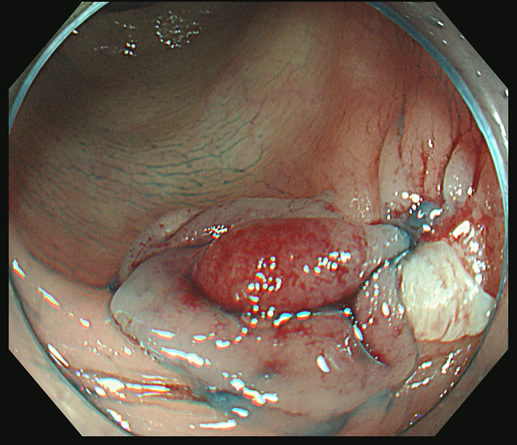

スネアー・ワイヤーを周囲の正常粘膜を巻き込みながら「広め」にかけます

十分なマージンを確保することを目指しますが、

右上方向が「ギリギリ」であることが解ります

カンシで右上方向を追加切除します